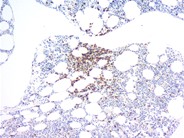

A CD20 (L26)immunostain for the presence of B-cells shows only a rare positive cell to be present.